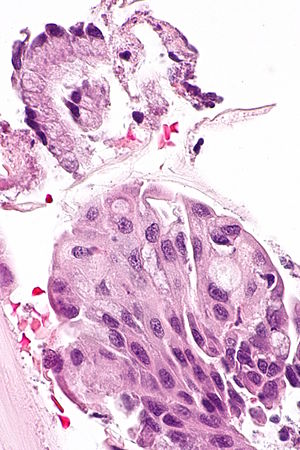

Squamous metaplasia and endocervical epithelium. H&E stain. | |

| LM | uniform cell spacing (no "crowding"), nuclei are uniform size and round, +/-nucleoli, distinct cell borders +/- intercellular bridges visible (common), adjacent/closely associated with endocervical epithelium - classically sits on surface (immature metaplasia), mitoses - rare, usually no nuclear hyperchromasia |

- Uniform cell spacing - no crowding - key feature.

- Nuclei are uniform size and round.

- Nucleoli present.

- Distinct cell borders

- +/-Intercellular bridges (due to edema) - common.

- Adjacent/closely associated with columnar epithelium.

- Columnar epithelium superficial in immature metaplasia.